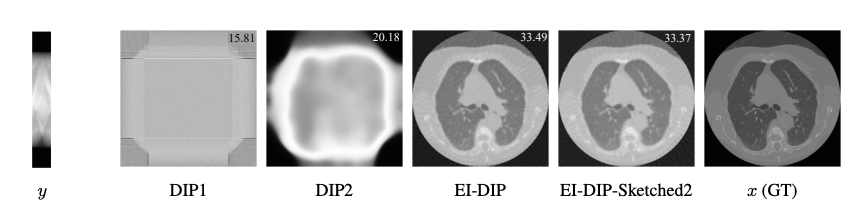

Equivariant Imaging (EI) regularization has become the de-facto technique for unsupervised training of deep imaging networks, without any need of ground-truth data. Observing that the EI-based unsupervised training paradigm currently has significant computational redundancy leading to inefficiency in high-dimensional applications, we propose a sketched EI regularization which leverages the randomized sketching techniques for acceleration. We then extend our sketched EI regularization to develop an accelerated deep internal learning framework -- Sketched Equivariant Deep Image Prior (Sk.EI-DIP), which can be efficiently applied for single-image and task-adapted reconstruction. Our numerical study on X-ray CT image reconstruction tasks demonstrate that our approach can achieve order-of-magnitude computational acceleration over standard EI-based counterpart in single-input setting, and network adaptation at test time.